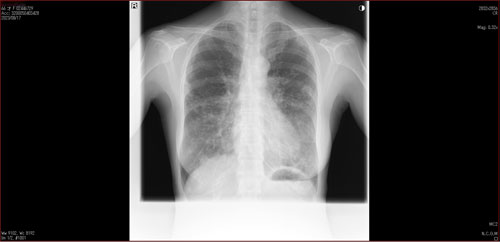

肺X線画像

- 2023.08.17 肺炎後の要観察(2)(国立系病院)